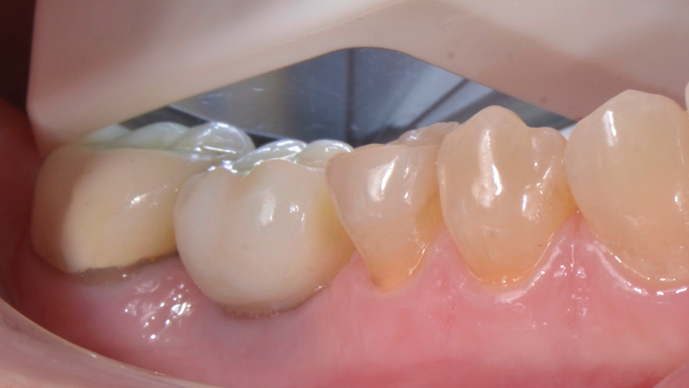

Iniciamos o planejamento com o escaneamento intraoral e uma tomografia computadorizada cone beam da mandíbula. De posse das informações, foi realizado o planejamento virtual do implante no Exoplan (Exocad) e o desenho e impressão da guia cirúrgica, bem como de uma coroa provisória CAD/CAM. A cirurgia guiada foi realizada com o Kit Implaguide CM 3.5, seguindo a sequência de fresas preconizadas pela Implacil De Bortoli. Foi instalado o implante Maestro de 3,5x11mm (Figura 1) e, logo após, o pilar Ideale 4,5x4x2,5. A coroa provisória CAD/CAM foi capturada utilizado a coifa provisória de titânio do pilar ideale(Figura 2). Após 60 dias de pós-operatório, a coroa provisória foi removida e observada em excelente perfil de emergência (Figura 3). Solicitamos uma nova tomografia e começamos a planejar a coroa definitiva, num fluxo restaurativo 100% digital com o iTero.